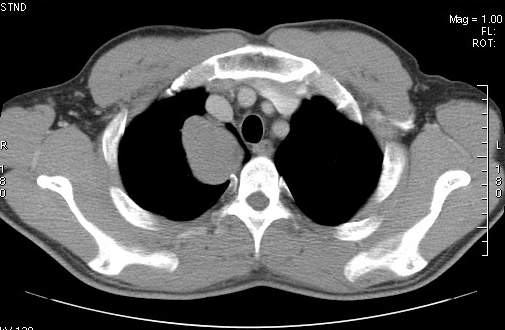

标题: CT7610:[原创]右上纵隔还是肺内占位,请会诊!

体检发现,无任何不适。

右肺见纵隔旁见类圆形界清等密度肿块影,直径约5.0cm,增强呈不均匀强化,重建的图片上看到肿块内可见强化的血管影,考虑:1,肺腺瘤;2,肺肉瘤。